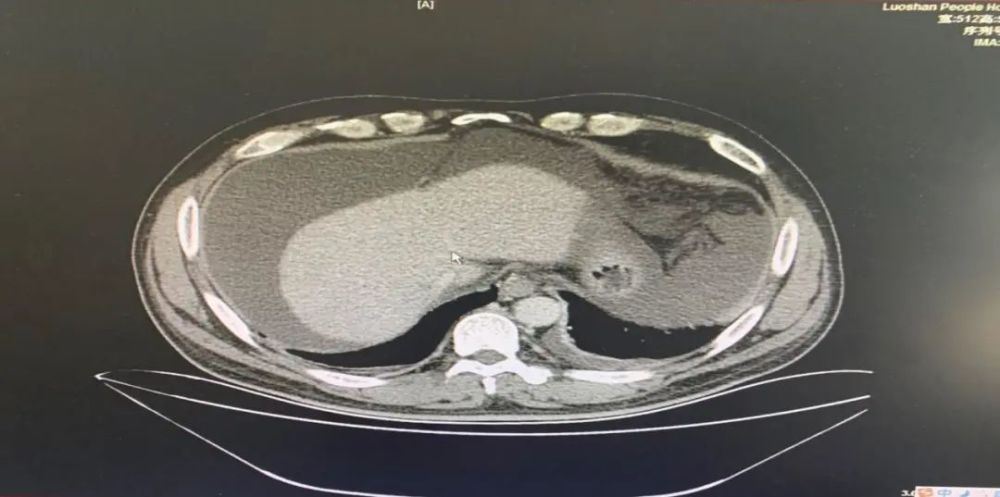

患者 , 男 , 47岁 , 发现双眼巩膜黄染伴腹胀一月 , 行上腹部CT(平扫):腹水;左侧胸腔少量积液;门诊以1.黄疸待查2.肝功能不全”收入院 。

该患者的肝纤四项结果异常引起我们的注意 , 翻阅患者电子病历 , 提示黄疸待查 , 患者精神差 , 影像学显示肝部增生异常 。

▲CT报告结果